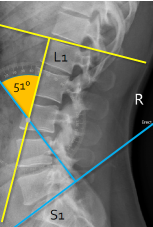

Q what is the name of this measurement? and what is the average + range?

A: Lumbar Lordosis

assesses the curvature of the lumbar spine. The normal range is 50-60°.